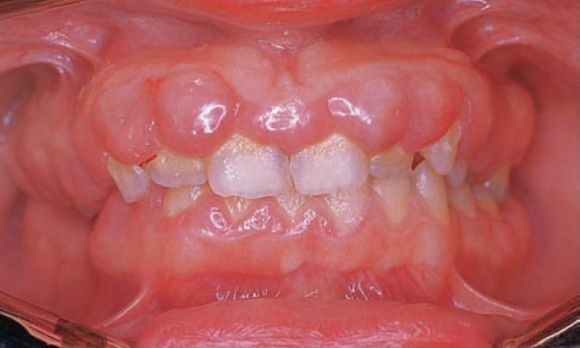

Generalized gingival hyperplasia

Firm, increased bulk of free and attached gingiva; usually asymptomatic; pseudopockets are mostly found.